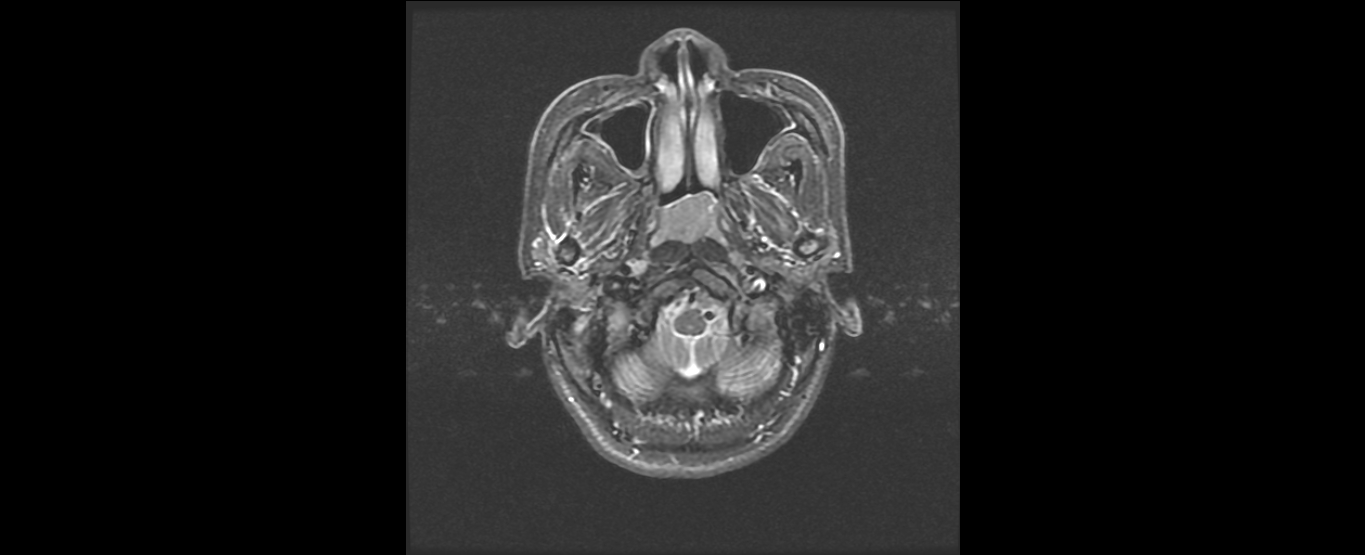

患者韦某某,女,37岁,2016年8月诊断为:鼻咽非角化未分化型癌(T2N2M0 III期),诱导化疗后行鼻咽癌根治性调强放疗,同期顺铂化疗,放疗结束后案辅助化疗。治疗结束复查见患者鼻咽肿物及颈部淋巴结均消退,疗效良好,目前随访1年患者各项检查指标完全恢复正常,已经恢复正常生活和工作。

放疗前鼻咽部MRI